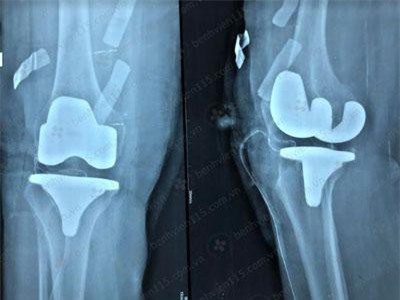

Từ 26/5 - 2/6, Bệnh viện Quân Y 175 (TP.HCM) sẽ tiến hành phẫu thuật nhân đạo thay khớp háng, khớp gối cho khoảng 50 bệnh nhân nghèo.